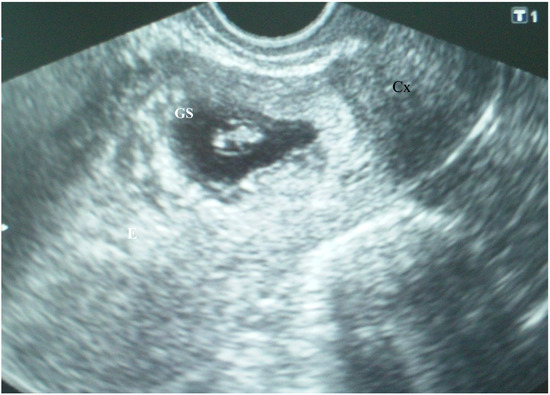

The patient’s laboratory results were within normal limits. Cesarean scar ectopic gravidity was suspected, and the patient was informed of the evolution to placenta previa, possibly to accreta, as well as of the associated risks. She was offered the option of termination. The patient, however, refused the termination of the pregnancy. Six days later, the patient was asymptomatic, and her abdominal pain disappeared, TVUS revealed a gestational sac containing an embryo with heart action and a crown–rump length (CRL) of 9.6 mm, which corresponded to 7 weeks and 1 day of gestation (Figure 2).

Figure 2.

Cesarean scar pregnancy: A gestational sac (GS) containing an embryo with heart action and a crown–rump length (CRL) of 9.6 mm, which corresponded to 7 weeks and 1 day of gestation.

The apparent larger thickness of the myometrial layer on the ultrasound examination performed during the eighth postmenstrual week (Figure 2) could be explained by the unequal thickness of the myometrial layer over the gestational sac along the cesarean scar and the development of the gestational sac toward the uterine cavity. Therefore, it seems that an ultrasound examination performed earlier in pregnancy is more accurate in predicting the severity of placenta accreta spectrum disorder.